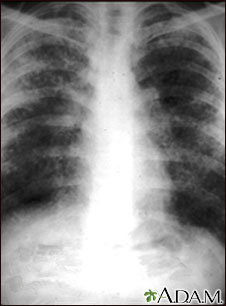

Sarcoid, stage II - chest x-ray

Sarcoid causes damage to the lung tissue that heals by scarring. The film shows a diffuse milky and granular appearance in the normally dark lung areas. This individual has marked decrease in lung function.